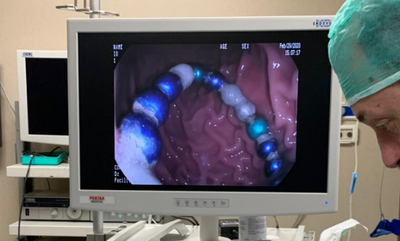

עקב השהות הממושכת של המגנטים במערכת העיכול, והיצמדות חלקים מצינור העיכול האחד לשני ע"י המגנטים, חדרו כמה מגנטים את דופן הקיבה, ולא ניתן היה לשלוף אותם מבלי לסכן את חיי הפעוט. בעקבות זאת הוכנס התינוק לניתוח חירום, לאחר הניתוח הוא הועבר במצב טוב למחלקה (חדשות בריאות)

בן שנתיים בלע מגנטים והובהל לבית החולים, שם הבהירו כי חיין בסכנה, מכיוון שכאשר הפעוט בולע יותר ממגנט אחד, הם נצמדים זה לזה בתוך מערכת העיכול ועלולים לגרום לקרעים במעיים ואז תכולת המזון במעיים נפלטת אל הבטן, לאחר הניתוח, חיי הפעוט ניצלו (חדשות)

תינוק שהובהל למרכז הרפואי 'אסותא אשדוד' לאחר שבלע מגנטים, ניצל בזכות טיפול מיידי שקיבל שלא כלל ניתוח • הרופאים מזהירים: "סביבונים מנגנים מסוכנים" (בריאות)

למרכז הרפואי מאיר הגיע ילד כבן שמונה ששיחק במגנטים ובלע 20 מהם בעודו משחק אצל חבר • ד"ר זיפמן מסר: "המגנטים נמצאו במעי הגס והוצאו בהצלחה לאחר ניתוח" • הילד נשאר למעקב צמוד לבדיקה שהכל תקין • איך נמנע את המקרה המסוכן הבא? (בריאות, חדשות)

ילד בן 5 שסבל כאבי בטן והקאות, התפנה ל'איכילוב שם הוא הובהל לחדר הניתוח ותחת הרדמה כללית הוצאו מקיבתו ארבעה מגנטים אותם בלע במהלך משחק. תמונות (בריאות)